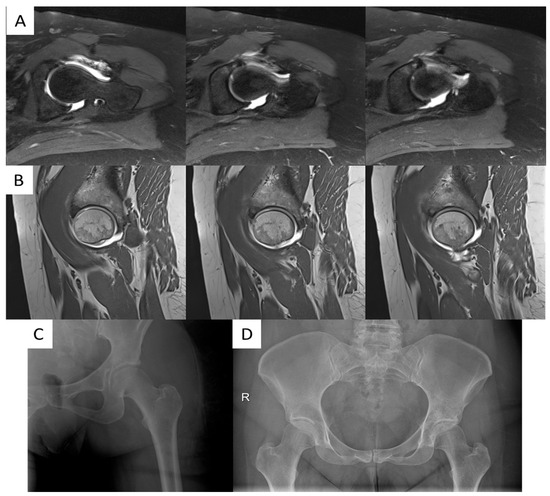

Tractionless Arthroscopic Treatment of Suspected Hip Septic Arthritis in Adults: A Single-Center Retrospective Case Series with Minimum One-Year Follow-Up

by Nadav Graif, Ran Atzmon, Aimee Steen, Shai Factor, Samuel Belmont, Michal Dekel, Ehud Rath and Eyal Amar

Surg. Tech. Dev. 2025, 14(4), 43; https://doi.org/10.3390/std14040043 - 4 Dec 2025

Background: Septic arthritis of the hip (SAH) requires emergent surgical intervention. While open arthrotomy has been the traditional approach, arthroscopic treatment is emerging as an effective alternative. Tractionless techniques in adult populations remain understudied. Methods: Twenty-one patients (22 hips) met inclusion criteria. Six [...] Read more.

Background: Septic arthritis of the hip (SAH) requires emergent surgical intervention. While open arthrotomy has been the traditional approach, arthroscopic treatment is emerging as an effective alternative. Tractionless techniques in adult populations remain understudied. Methods: Twenty-one patients (22 hips) met inclusion criteria. Six patients (7 hips) were excluded for age < 18 years, post-COVID osteomyelitis, prior hip surgery, or insufficient records, resulting in a final cohort of 15 patients. All fifteen patients underwent tractionless arthroscopic irrigation and debridement for suspected SAH (2014–2023). Inclusion required ≥2 clinical criteria (hip pain, limited range of motion, inability to bear weight, fever > 38 °C) AND ≥ 1 laboratory criterion (leukocytosis, elevated CRP, synovial WBC > 50,000, positive culture). Primary outcomes included Visual Analog Scale pain scores, inflammatory markers, and complications. Results: Median age was 33 years (range 20–76); 60% were female. VAS scores improved from 7 (6–10) to 1 (0–3) at discharge (p < 0.001). CRP levels decreased from 115 mg/L (35–206) to <5 mg/L (<5–9) postoperatively (p < 0.001). Positive cultures were obtained in 26.7% of cases, predominantly methicillin-sensitive Staphylococcus aureus. No perioperative complications occurred. Histopathological analysis revealed tenosynovial giant cell tumor (TGCT) in 33.3% of cases, representing an important differential diagnosis. Among non-TGCT cases, the culture-positive rate was 40%. No infection recurrence was observed during a minimum one-year follow-up. Conclusions: Tractionless arthroscopic irrigation and debridement appears effective for managing suspected SAH in adults, achieving significant improvements in pain scores and inflammatory markers without perioperative complications. This technique offers potential advantages by eliminating traction-related risks while maintaining effective joint debridement. Additionally, TGCT should be considered in the differential diagnosis of suspected SAH with culture-negative inflammatory arthropathy. Full article

Show Figures

Figure 1